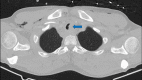

Tracheobronchial injury (TBI) is a rare life-threatening injury that can result from either penetrating or blunt trauma. Treatment may be surgical or conservative, but the evidence regarding which is the best approach is still very scarce. This case report describes the successful conservative management of a 32-year-old male with a traumatic tracheal laceration. The alarming signs and symptoms, the imaging modalities of choice, the rationale behind the treatment strategy, and the most common complications are detailed here. Through this case, the authors wish to highlight the features that should lead to the suspicion of this potentially fatal traumatic injury, as well as raise awareness on how to adequately manage these patients.